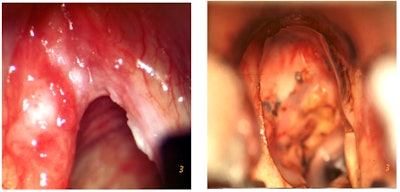

CO2 laser surgery has a shorter recovery time than XRT. This is because the procedure is less invasive and does not involve the use of ionizing radiation, which can cause long-term fatigue and other side effects. This allows patients to return to their normal activities more quickly. As such, this patient undergoes TOLMS with the pre- and postoperative photographs as shown in Figure 1, receiving a type III laser cordectomy as published by the European Laryngological Society (ELS).

Figure 1. Pre- and postoperative photographs of patient who underwent TOLMS.

Photos courtesy of Marc Remacle, MD, PhD.